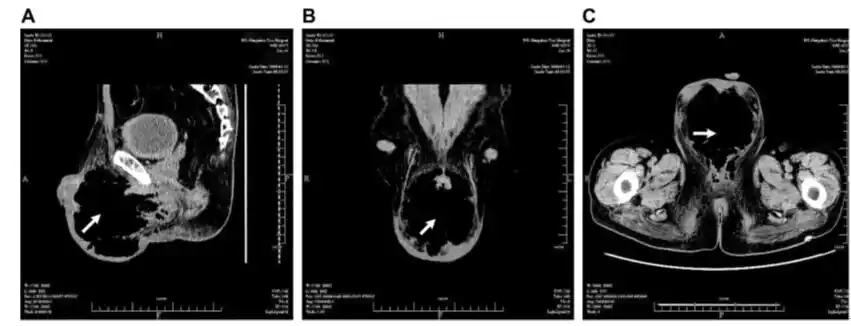

图1.(a)矢状位,(b)冠状位及(c)轴位ct扫描

可见典型的" 丝瓜瓤症", 其内可见多个斑点状更长t 2信号影;b,c:轴位